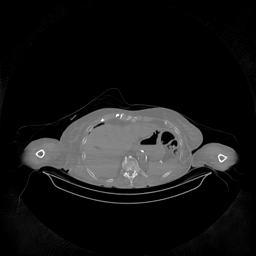

The results for simulated noisy data are shown in Fig. 2. The first and third rows display two representative slices from the test set, and the second and fourth rows present the corresponding error maps. The traditional WCE method suppresses cupping artifacts and recovers some missing anatomical structures but still shows noticeable deviations from the ground truth. Predictions from the four diffusion-based models demonstrate a markedly improved ability to restore anatomical structures. Among them, cDDPM fails to fully reconstruct the patient bed and retains residual noise in its outputs. This noise is attributable to an incomplete reverse denoising process rather than residual Poisson noise, as evidenced in our noise-free experiments (Fig. 5 in the Appendix). PatchDiffusion, diffusionGAN, and I2SB achieve similar visual quality, with I2SB producing the cleanest and most consistent reconstructions.

The experimental results on clinical head data are shown in Fig. 4. The reference images were reconstructed using the fast iterative shrinkage-thresholding algorithm (FISTA) with total variation regularization from non-truncated projection data. In the WCE reconstructions (Fig. 4(b)), severe truncation prevents accurate recovery of anatomical structures outside the FOV. Despite being trained solely on simulated data with a domain gap, all deep learning models can restore a substantial portion of the missing anatomy. Among them, the diffusion-based methods recover soft-tissue boundaries more faithfully than the conventional deep learning approach FBPConvNet, highlighting their stronger image generation capability. However, cDDPM reconstructions exhibit more noticeable noise than those from other methods, consistent with the simulated data results. The patchDiffusion model introduces artifacts within the FOV, likely due to its patch-wise processing strategy. While I2SB shares the same limitations as other diffusion models in perfectly restoring soft-tissue detail, it produces fewer residual noise patterns and fewer artifacts within the FOV boundaries. Overall, Fig. 4 demonstrates the strong efficacy of I2SB in reconstructing real CBCT data.